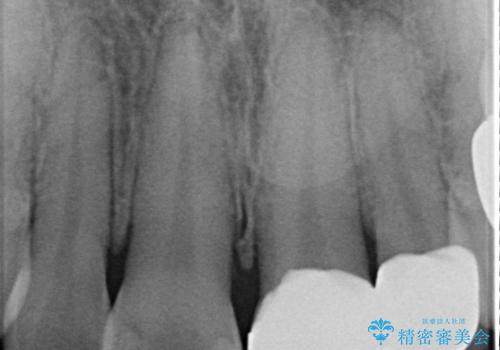

- 「前歯の色が気になる」を主訴に来院された患者さんです。以前他院にて、前歯2本をCR(プラスチック)で治療されていたところが劣化し変色していました。歯の長さも左右で異なっている状態でした。大部分がCR(プラスチック)修復されていたので、オールセラミッククラウンで治療を行いました。

古いCR(プラスチック)とその下の虫歯を除去した後に新しい土台を立てています。適合が良い被せ物を作るために拡大鏡を使用しながら歯を削り、変形のほとんどないシリコンという材料で型取りを行っています。